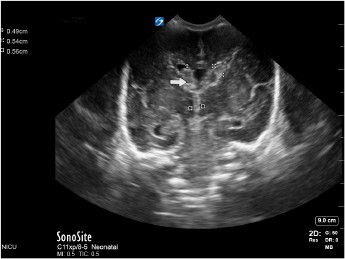

Neonatology Anterior Fontanelle 3rd Ventricle 2 Image